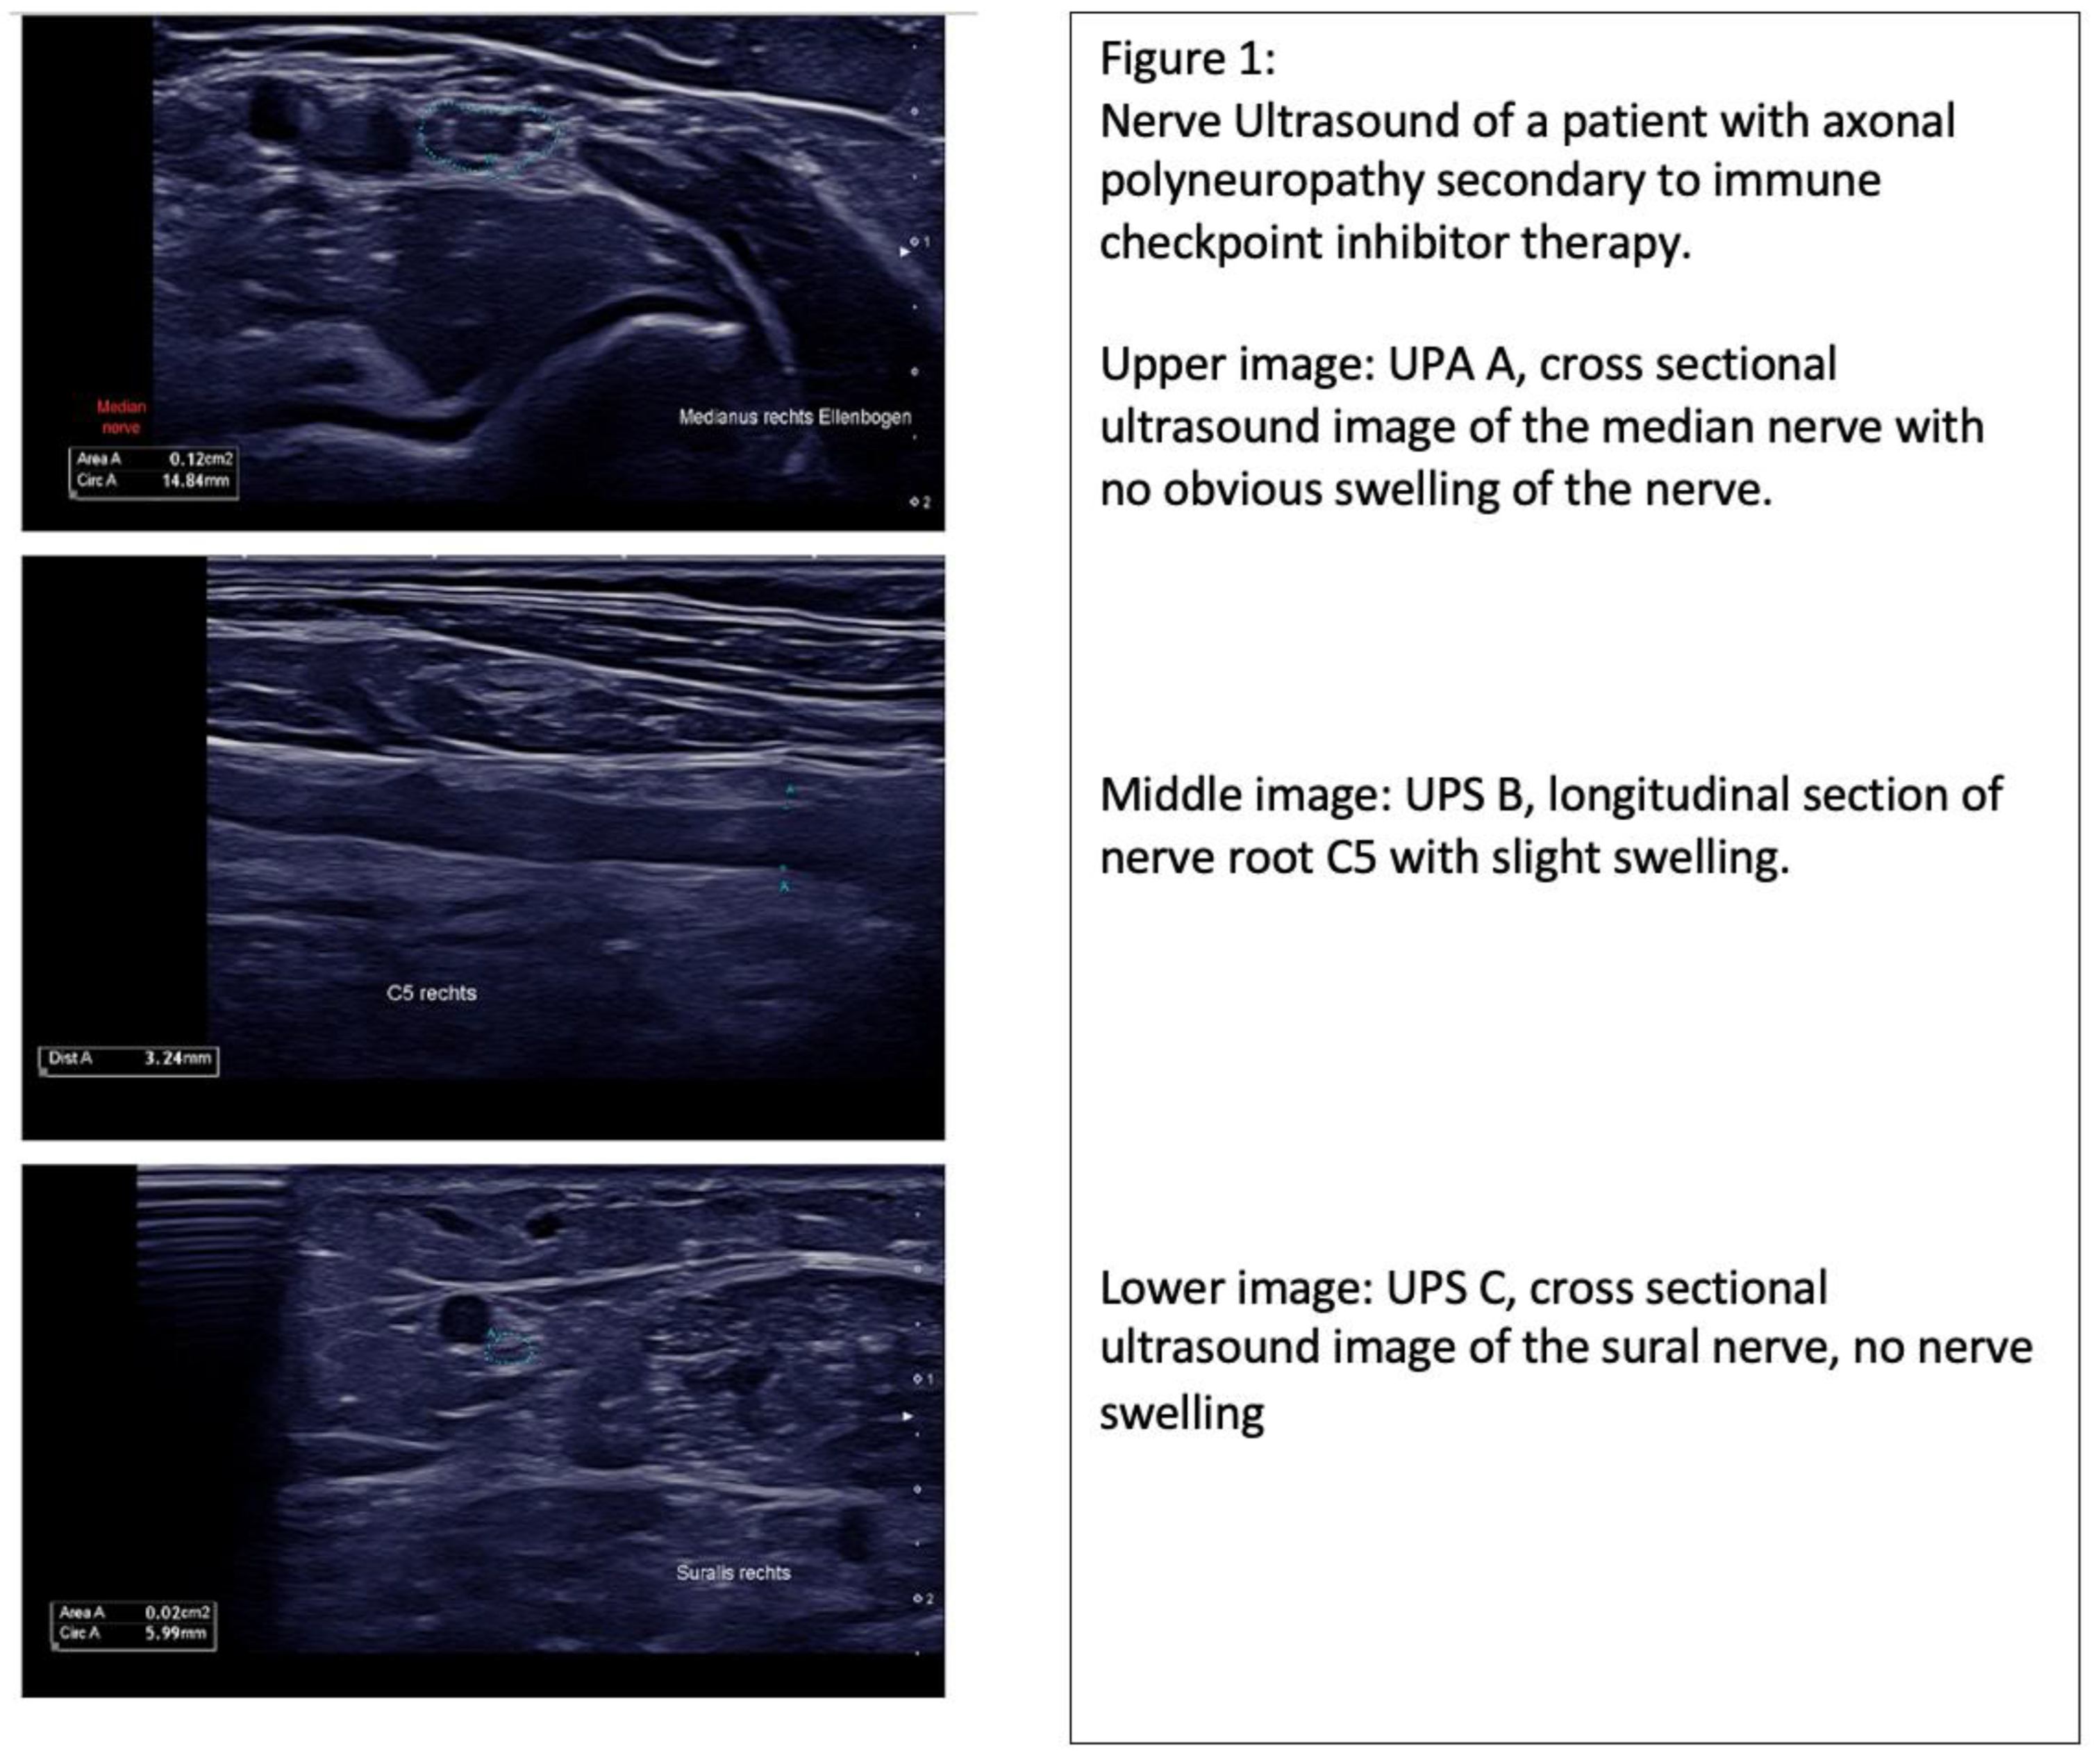

| 1 | 77 | M | Melanoma | Ipilimumab/Nivolumab | 5 UPS A 2 UPS B 2 UPS C 1 | Inconclusive | N/A | N/A | N/A |

| 2 | 56 | M | Small-cell lung carcinoma | Atezolizumab | 2 UPS A 0 UPS B 2 UPS C 0 | Axonal PNP | 10/µL cells, 156 mg/dL protein | IVIG | Negative |

| 3 | 53 | F | Melanoma | Atezolizumab | N/A | Axonal PNP | N/A | N/A | N/A |

| 4 | 65 | F | Melanoma | Ipilimumab/ Nivolumab | 2 UPS A 1 UPS B 1 UPS C 0 | Axonal PNP | 19/µL cells, 100 mg/dL protein | CS | Negative |

| 5 | 55 | F | Melanoma | Ipilimumab/ Nivolumab | 2 UPS A 2 UPS B 0 UPS C 0 | Axonal PNP | 26/µL cells, 1117 mg/dL protein | IVIG | Negative |

| 6 | 78 | M | Aesthesioneuroblastoma | Nivolumab | N/A | Axonal PNP | 18/µL cells, 144 mg/dL protein | N/A | N/A |

| 7 | 79 | M | Melanoma | Nivolumab | 0 UPS A 2 UPS B 0 UPS C 0 | Axonal PNP | 9/µL cells, 40 mg/dL protein | CS | Negative |

| 8 | 86 | M | Urothelial Ca | Pembrolizumab | 3 UPS A 1 UPS B 2 UPS C 0 | Axonal PNP | 13/µL cells, 77 mg/dL protein | IVIG | Negative |

| 9 | 68 | M | Urothelial Ca | Pembrolizumab | 2 UPS A 2 UPS B 0 UPS C 0 | Axonal PNP | 9/µL cells, 32 mg/dL protein | IVIG | Negative |

| 10 | 58 | F | Melanoma | Ipilimumab/ Nivolumab | 0 UPS A 0 UPS B 0 UPS C 0 | Axonal PNP | 22/µL cells, 72 mg/dL protein | IVIG | N/A |